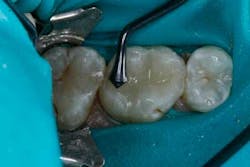

The tooth was prepared and a total etch technique utilizing 37% phosphoric acid was performed (Figs. 3 through 5). After the etchant was rinsed, a desensitizer was placed and blotted to leave a moist dentin surface for bonding (Fig. 6). The bonding agent was applied; the ethanol solvent was air evaporated using a warm air dryer; and the adhesive light-cured for 10 seconds (Figs. 7 and 8).

Fig. 6.